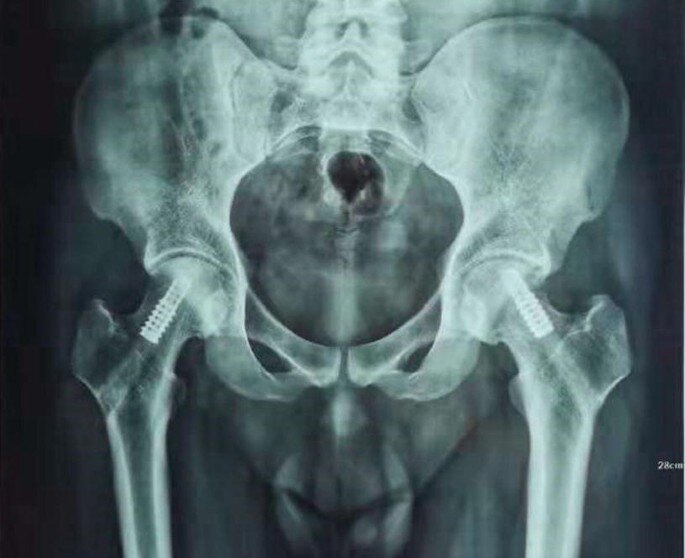

股骨頭壞死早中期經(jīng)常面臨兩個問題:一、容易誤診、漏診,以至于失治誤治;二、治療方法選擇困難,對手術(shù)與否、何時手術(shù)心存疑慮,甚至錯過最佳治療時機。希望本案例可提供一點借鑒。男性,41歲,2016年12月主訴“不明原因右臀部疼痛”以雙側(cè)股骨頭壞死為診斷住院治療。在當?shù)蒯t(yī)院磁共振檢查確診,左側(cè)壞死尚無癥狀。在我院CT檢查示:X線檢查:術(shù)中所見:我們采用外科脫位技術(shù),充分暴露股骨頭,經(jīng)圓韌帶窩窗口挖出死骨并進行植骨。術(shù)中見關(guān)節(jié)面軟骨發(fā)生退變,死骨松軟如豆腐渣。術(shù)后復(fù)查:術(shù)后1年復(fù)查:術(shù)后3.5年復(fù)查:骨吸收是股骨頭壞死修復(fù)過程中非常棘手的問題,必須采取積極措施阻止進一步惡化。通常會采取多種方法,包括藥物治療、高能聚焦沖擊波治療等。半年后再次復(fù)查:又過了1年,術(shù)后第5年復(fù)查:術(shù)后7年復(fù)查:術(shù)后8年復(fù)查:至于左側(cè)股骨頭壞死,因為面積較小,簡單采用中藥、沖擊波治療,一直情況穩(wěn)定,這次就不展開贅述。如下:幾句話總結(jié)1.年輕股骨頭壞死保頭要趁早,切莫沉醉在所謂“秘方”的幻想中,建議通過全面檢查評估制定周全的治療方案;2.大約2/5的早中期病例可通過保守治療控制病情,但需要手術(shù)的情況也不能視而不見,理性、客觀對待病情;3.股骨頭壞死的病情轉(zhuǎn)歸十分復(fù)雜,別人成功的經(jīng)驗一定不是放之四海而皆準,除了因人而異進行治療之外,必須堅持定期復(fù)查、長期觀察,以準確掌握病情變化,在關(guān)鍵節(jié)點調(diào)整治療措施;4.任何一種單一治療措施發(fā)揮的作用總是有限的,就如做飯放調(diào)料,某一種佐料看似不起眼,缺一樣就少一種味道,和諧搭配才能取得最佳效果。同樣,藥物治療、物理治療,甚或手術(shù)治療需要有機結(jié)合,切莫盲目相信某一種方法的“神奇”效果。